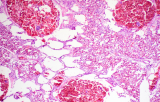

- Tejido conjuntivo: A.F.O.G, Tricrómico de Azan, Tricrómico de Masson, Tricrómico de Mallory ...